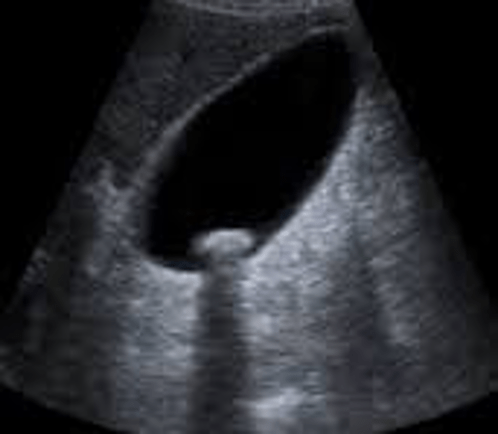

This image was produced by which type of transducer?

curvilinear array (or curved linear)